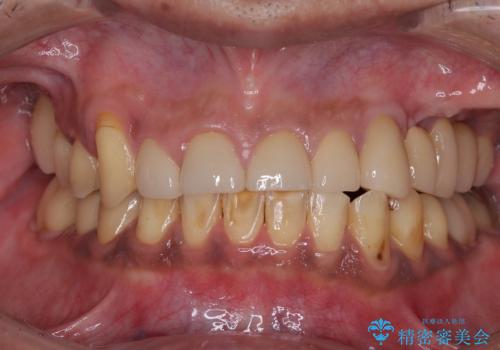

外れるブリッジと気になる八重歯 総合歯科治療で美しい口元に

歯周病 、インプラント、 矯正 全顎治療